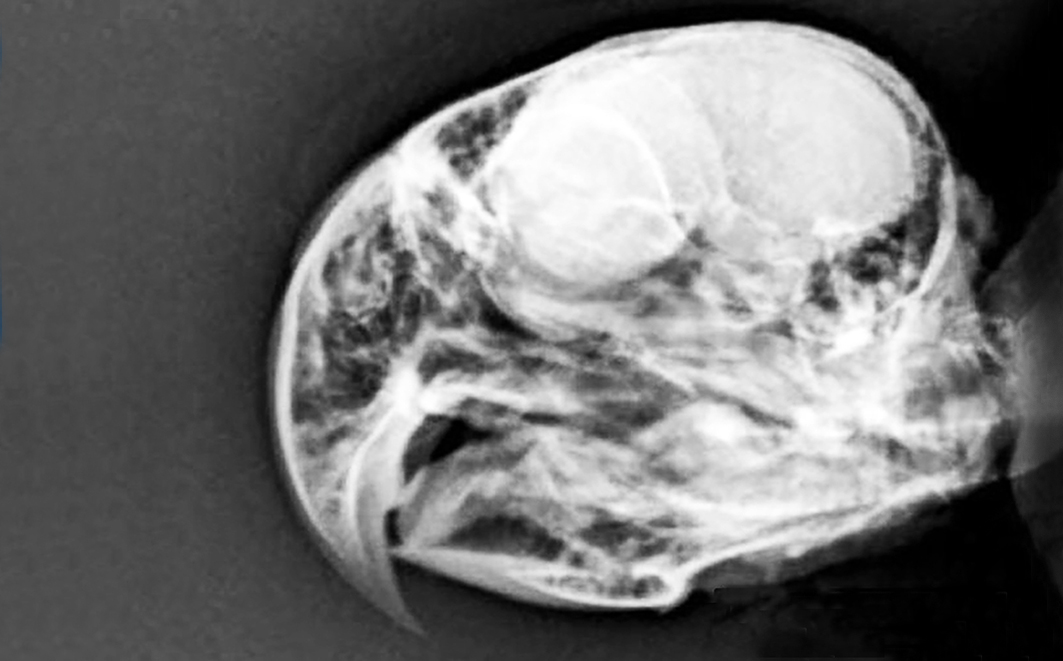

Um maracanã-nobre (Diopsittaca nobilis), sexo indeterminado, pesando 168 g (gramas), jovem, foi atendida em uma clínica particular, após ter sido encontrada por munícipe em via pública abaixo de um grande vitral em ponto comercial da cidade. Ao exame físico a ave apresentava-se com sinais de incoordenação motora, olhos fechados, lateralização de cabeça, hematoma em face lateral esquerda e sangramento pelas narinas (Figuras 2 e 3), hipotermia leve 39,2 °C graus, levando a suspeitas de trauma crânio encefálico. A ave apresentava sinais de Glasgow moderado sugestivo em 10.

Também foi realizado como exame complementar a radiografia de crânio para investigar lesões intra e extracranianas (Figuras 6 e 7). O mesmo apontou edema em região de olho direito (Figura 8). Nessa radiografia de crânio não se evidenciaram lesões extracranianas. Após 24 horas a ave demonstrou melhora clínica do quadro neurológico conseguindo deambular, mímica de vocalização e parcial abertura dos olhos (Figuras 9 e 10).